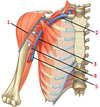

1: Cranial nerve XI (accessory nerve)

1? 2?

1: Levator scapulae muscle

2: Rhomboid major and minor muscles